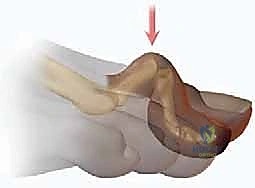

تثبيت مفصل الكاحل الأمامي: حل فعال لخشونة الكاحل المزمنة مع الأستاذ الدكتور محمد هطيف

تعرف على تثبيت مفصل الكاحل الأمامي لعلاج خشونة الكاحل المتقدمة. اكتشف الأعراض، التشخيص، والخطوات الجراحية مع الأستاذ الدكتور محمد هطيف في ص…